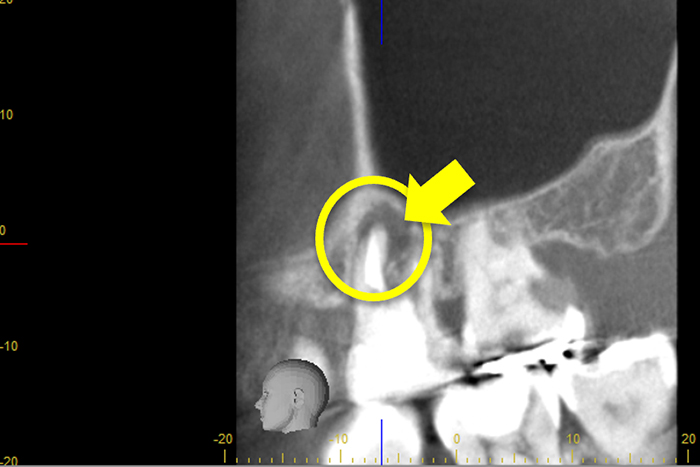

心臓の鼓動のように『ドク・ドク』と浸出液が出ているのが分かる。

| 主訴 | 何もしなくてもズキズキ痛い |

| 治療費 | 感染根管治療(大臼歯):88,000円 |

| 治療内容 | 急性症状改善のための排膿治療 |

| 治療のリスク | 抜歯のリスク |